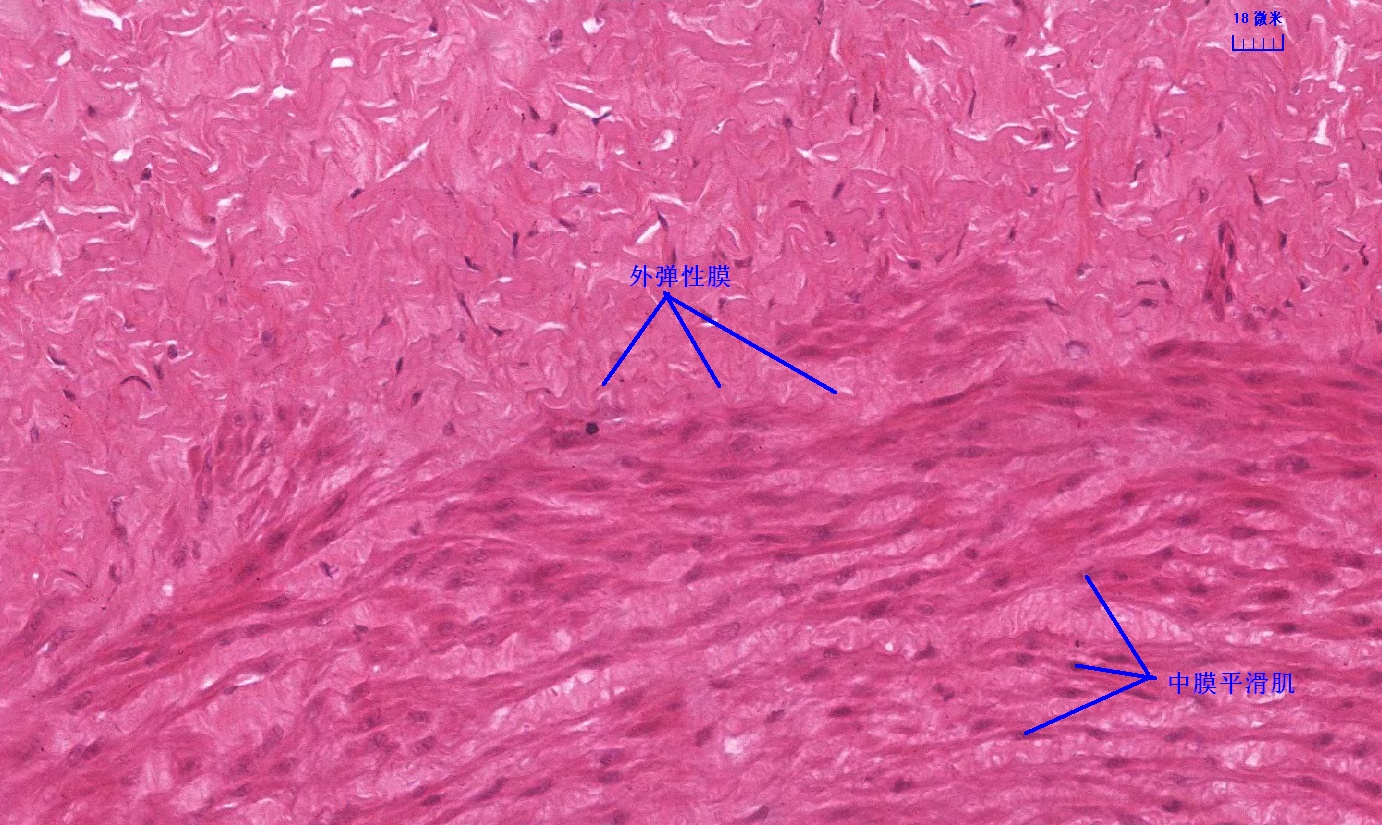

6 第六单元 循环系统

6.1 循环系统切片库

6.2 循环系统微课

6.3 循环系统课件